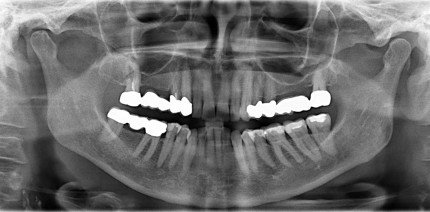

Fungusball in der Kieferhöhle nach Wurzelkanalbehandlung